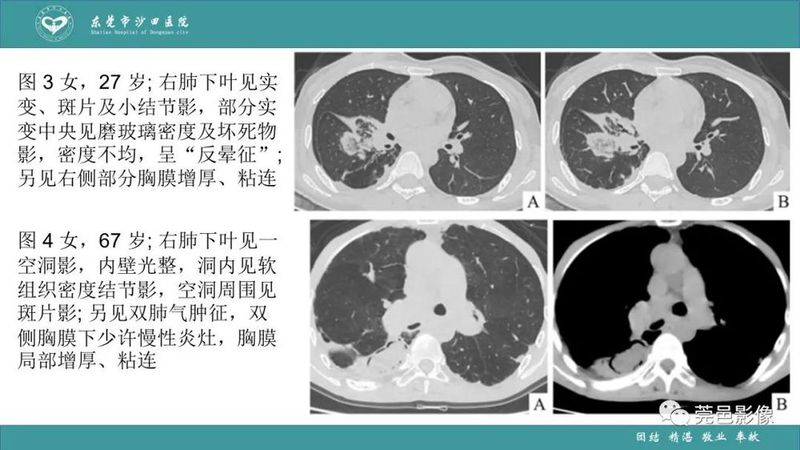

「肺炎克雷伯杆菌肺炎」影像学诊断+鉴别诊断